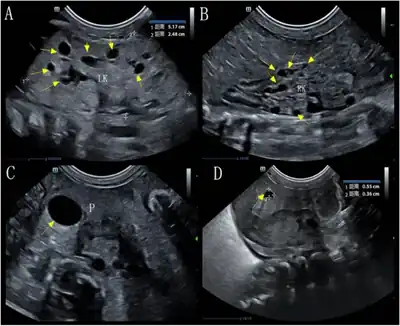

| Gross photo of liver and pancreas showing multiple cysts in the latter in a patient with renal–hepatic–pancreatic dysplasia | |

Renal–hepatic–pancreatic dysplasia is an autosomal recessive congenital disorder characterized by pancreatic fibrosis, renal dysplasia and hepatic dysgenesis. It is usually fatal soon after birth.An association with NPHP3 has been described.[1] It was characterized in 1959.[2][3]